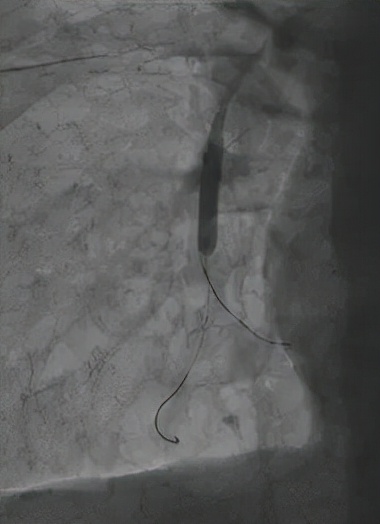

△球囊扩张狭窄血管

△球囊扩张后复查,血管血流明显改善

“人体的肺血管如同一棵大树,血栓常常堵在了‘树杈’、‘分支’部位,对狭窄血管进行扩张疏通,可以显著缓解肺动脉压力、血管阻力等问题。”介入手术过程中,医生需要身着厚重的防辐射铅衣,屏气凝神,在细微的血管间谨慎地完成每一项精细的操作,“如果稍有不慎,非常容易导致血管破裂,造成严重的并发症,非常考验操作者的经验与熟练度。”洪城副主任医师说,他们一次性为患者开通了8条血管,肺血管灌注后血流明显好转。